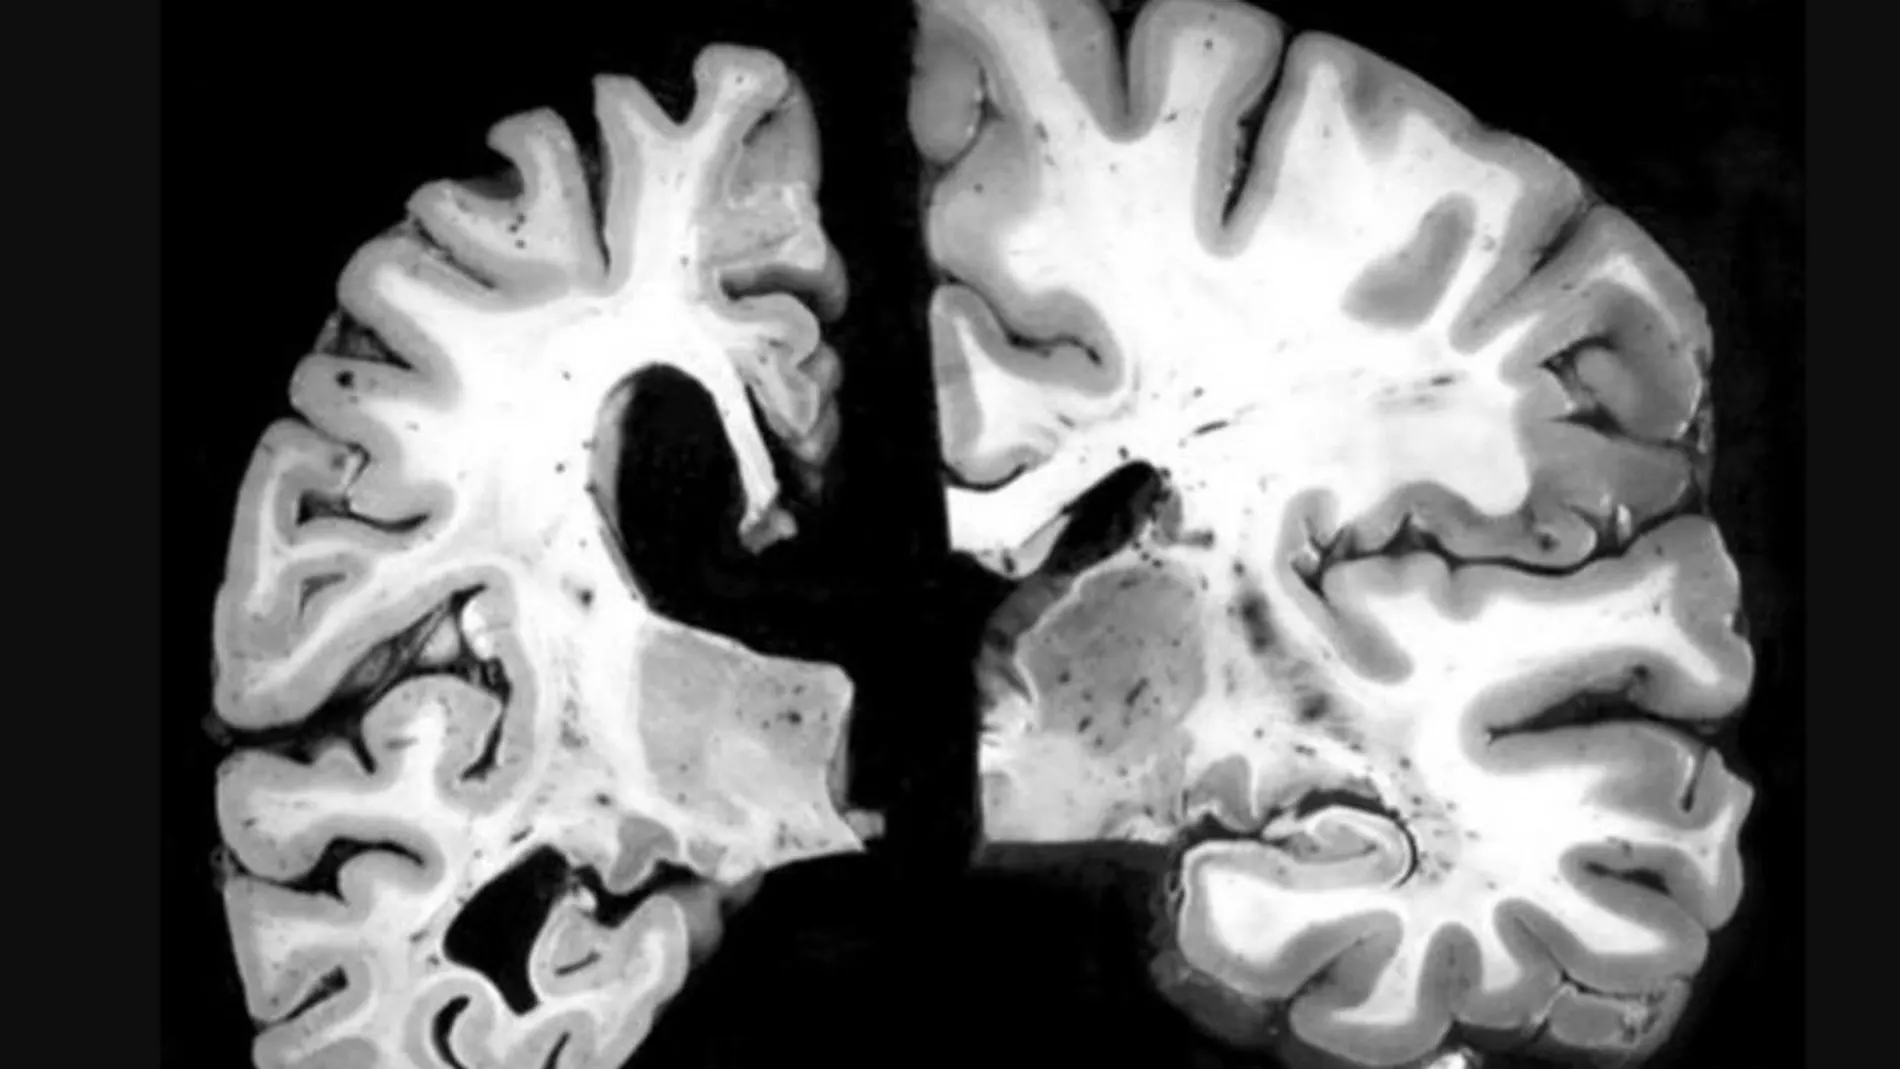

En concreto, ha detectado que el número de alelos e4 del citado gen determina de forma proporcional un volumen más pequeño de sustancia gris en áreas cerebrales como el hipocampo, donde empieza la neurodegeneración en el Alzheimer.

También han descubierto que la sustancia gris del tálamo, el lóbulo occipital y el córtex derecho frontal es más grande, por estar más inflamado, lo que podría estar determinado por mecanismos neuroinflamatorios asociados a la acumulación de placas de proteína betaamiloide, que tiene lugar en los primeros estadios.